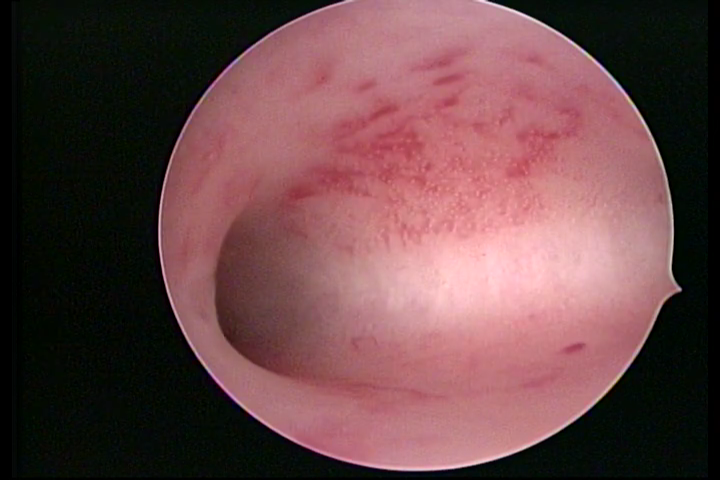

CHRONIC ENDOMETRITIS

The surface of the endometrium may present changes such as a red punctuate forming vascular balls, a smooth, hypervascularized endometrium or intensely presenting red areas, with accurate edges and yellowish white spots in its interior, providing a "STRAWBERRY PEEL" aspect, a pale yellow color of fundic and lateral commissures, in contrast with the intense red color present in the walls.